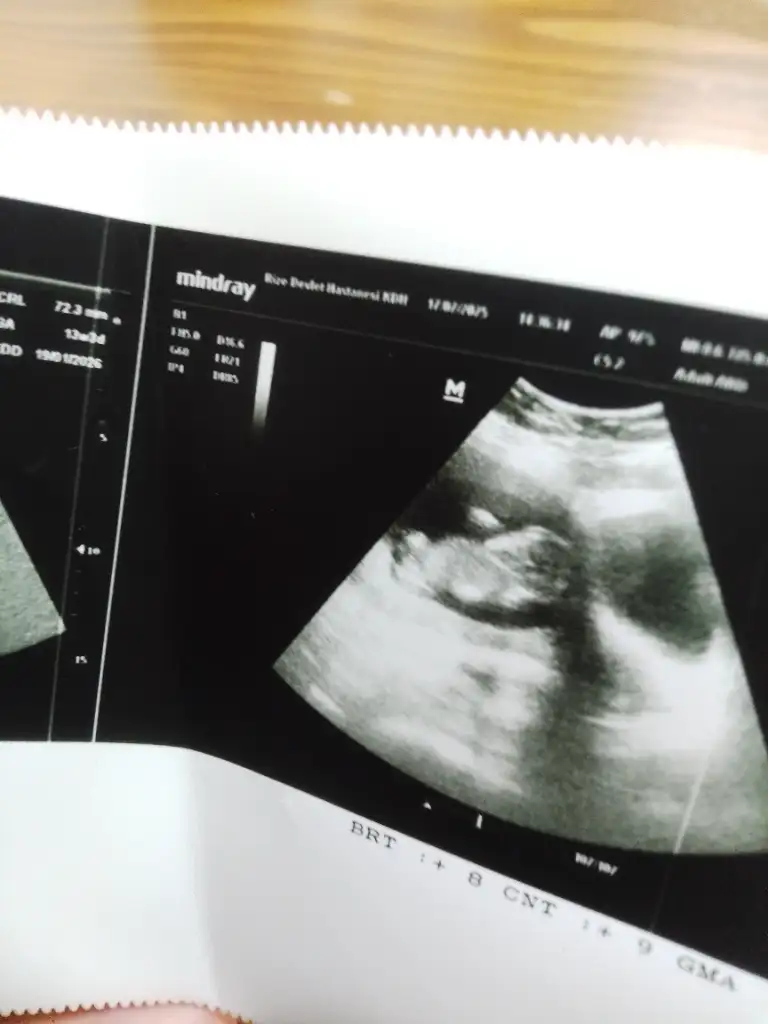

Yorum yaparmısınız. Biri 11hafta 6günlük. Diger 16 haftaKızzzz

kızYorum yaparmısınız. Biri 11hafta 6günlük. Diger 16 hafta

Erkek gibi geldi banaYorum yaparmısınız. Biri 11hafta 6günlük. Diger 16 hafta

Sizinde erkek

Erkek :) givi duruyor ama Allah gönlünüzdekini versinYorum yaparmısınız. Biri 11hafta 6günlük. Diger 16 hafta